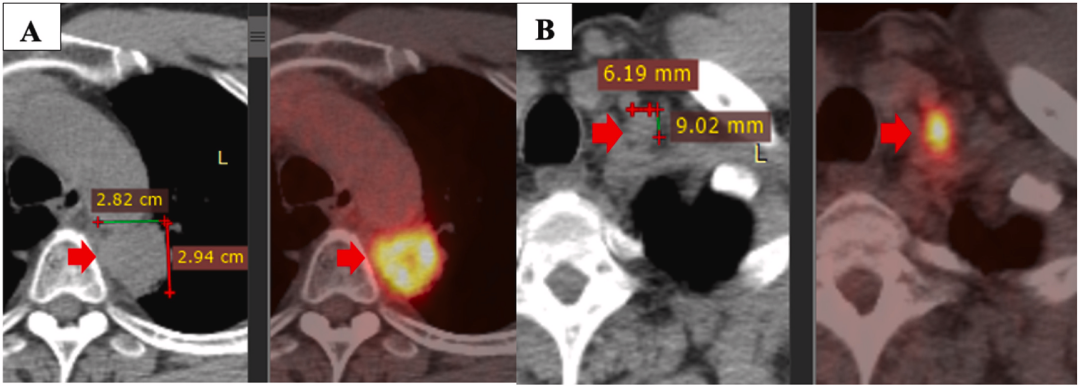

一线治疗一年后疾病进展:原发性肿瘤(A),左侧锁骨上淋巴结(B)

然而,患者的病情于2020年5月发生进展。PET/CT扫描显示原发肿瘤大小为28×29mm,最大标准化摄取值(SUVmax)为11.2,粘附纵隔胸膜和主动脉。此外,左侧锁骨上淋巴结的大小为9×6mm,左侧肺门中有几个小淋巴结的大小小于10mm。